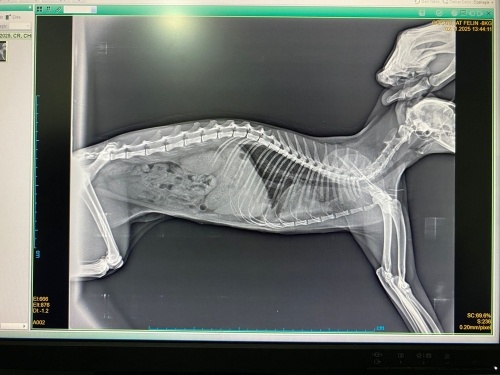

Merhaba iki gün önce kedim bir anda halsizleşti ve nefes almakta zorlandığını farkettim veterinerde akciğer filmi çekildi ardından test yapmak istediklerini söylediler fipten şüphelenerek yaptırdık ve sonra günlük fip iğnemizi ve 5 günlük sabah akşam şeklinde antibiyotiğimizi olmaya başladık bugün ikinciyi oldu halsiz olsa da arada keyfi yerine geliyor yemek azda olsa yiyor lakin benim evde 5 kedim daha var onlarada bulaşmış olma ihtimali beni korkutuyor kumlarını odalarını ayırdım ama napıcam bilmiyorum yardım edin

Her korona pozitif fip demek değil, akciğer filminden kesin olarak fip anlaşılabilir mi bilmiyorum ama kan tahlili yapılsa daha iyi olmaz mıydı? Albumin/globulin oranına bakılsa daha iyi olur diye düşünüyorum. Umarım bir an önce kediniz iyileşir 🌸

sevgili arkadaşlar her birinize çok teşekkür ediyorum kedimi hayvan hastanesine de muayeneye götürdüğümde kalpten şüphelendiler ardından kalp bölümüne gittiğimizde kalp kasında gevşeme benzeri bir sonuca varıldı ancak ilaçla tedavi edilebileceğini bu sorunun kalple ilgili olmadığını söylediler kalp ilacı aldık kullanıyoruz ayrıca hava ve yaklaşık üç ilaç daha kullandık diğer veterinerimizde fip gibi durmuyor dedi yarın tekrar kontrole götüreceği.m halen diğer kedilerle birarada değil ama verdiğiniz bilgiler için her birinize teşekkür ediyorum dua edin dostlarım Allah bir daha yaşatmasın ve sonuçlarımız iyi çıksın. Sizlere ve patili dostlarınızı sımsıkı kucaklıyorum sevgilerrrr